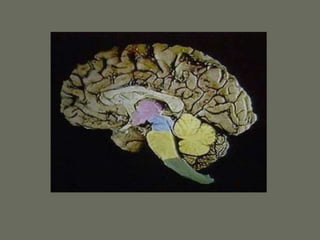

Parts of the Central Nervous

System

• 2 hemispheres

• Brainstem

• Cerebellum

• Spinal cord

Each hemisphere has lobes:

• Frontal lobe

• Parietal lobe

• Temporal lobe

• Occipital lobe

• Insular lobe

• Limbic lobe